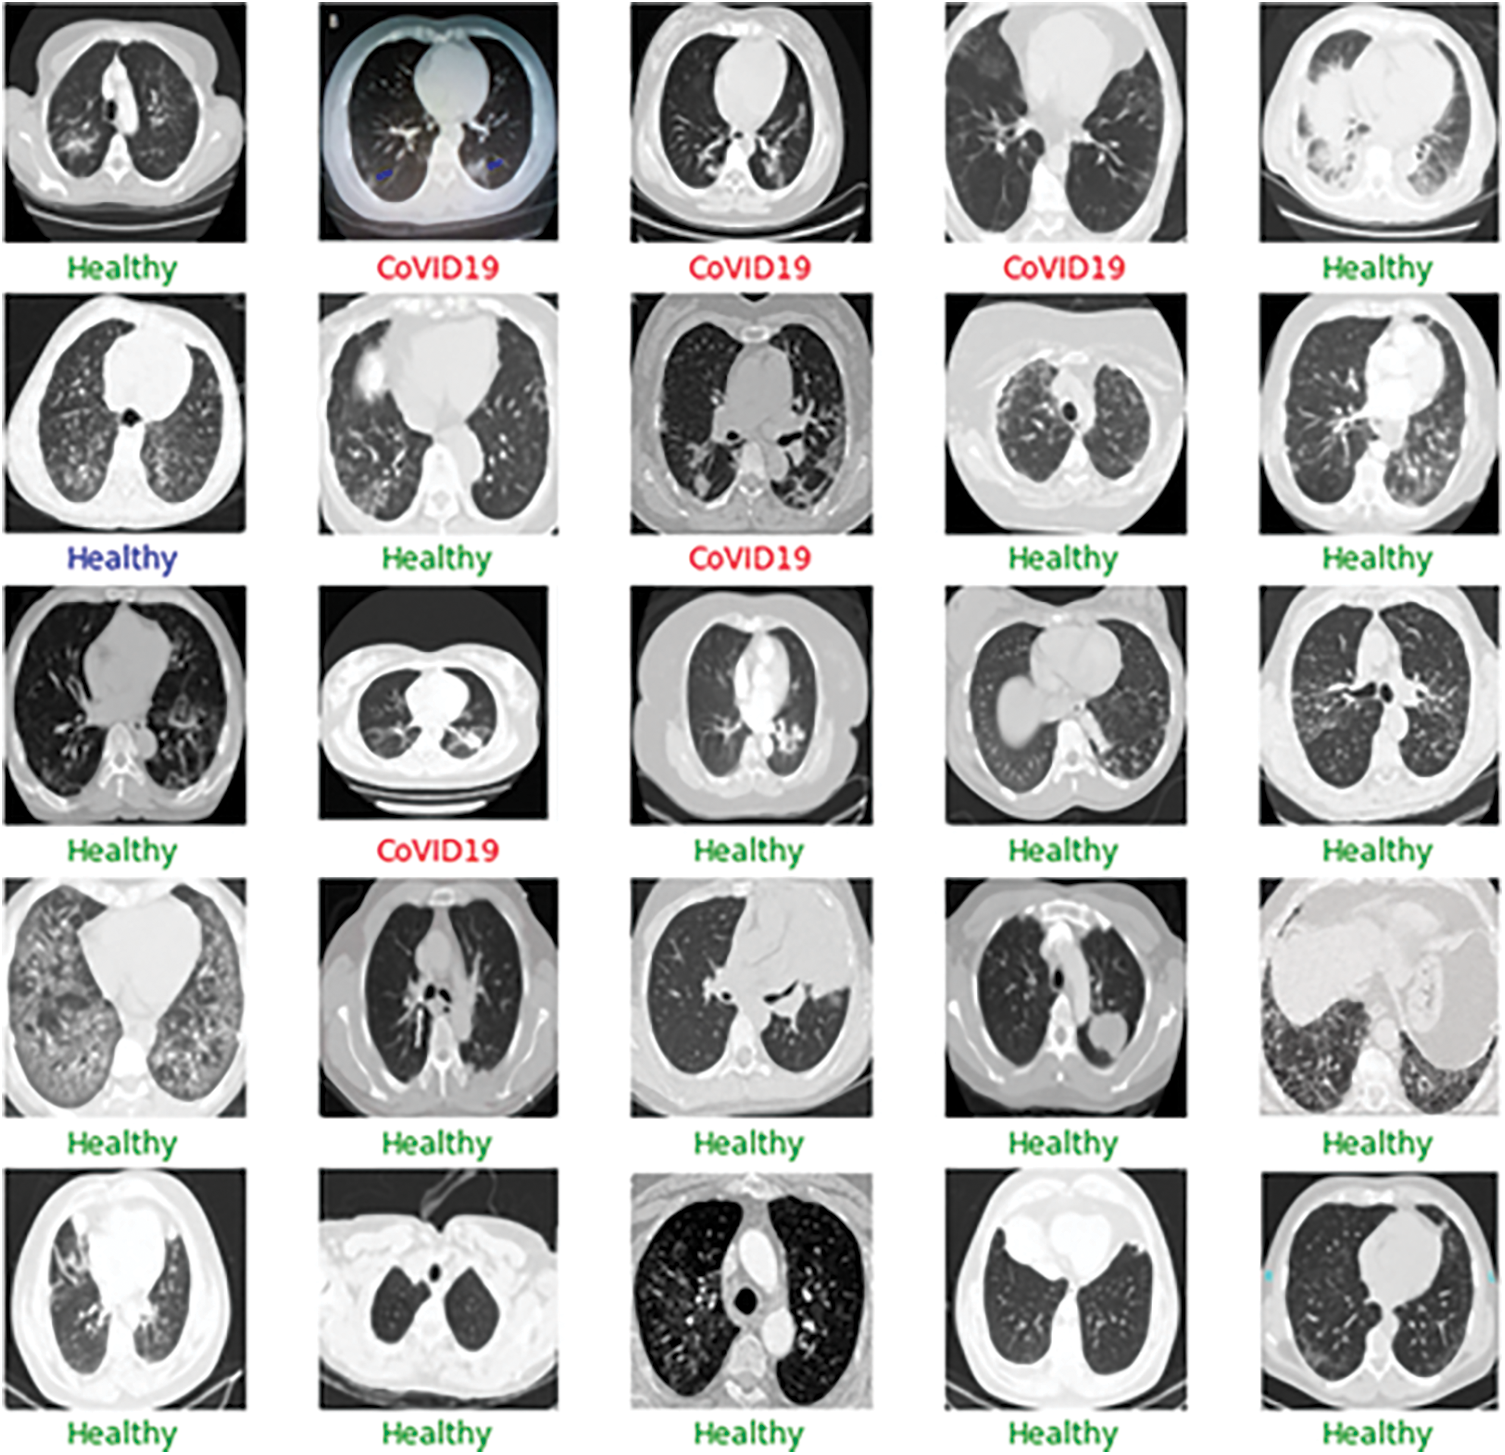

A similar procedure is followed in the case of CT-Scans as well. The CT COVID research publication provide the dataset that is utilized to create the model for automatic detection of the infected zone. This dataset contains CT images of 146 COVID-19 infected individuals and 397 images of healthy people. The OOS data is filtered to remove 22 photos from dataset two, including both X-Rays and CT-Scan images. The OOS data is then analyzed to determine the optimal model for infection detection in the future. We utilize the Holdout approach to construct the model. Seventy-five percent of the data is utilized in the training phase, while twenty-five percent is used in the validation process. The model that performs the best in both the validation and the OOS data can be deemed the best. As a result, the model must perform well in OOS data and in the validation sample to be judged superior to others. The performance of all pre-trained designs is compared in Tab. 3. Figs. 10 and 11 show examples of results.

Figure 11: Sample CT scans report for the training of the model for the detection of the COVID-19 infection

The DenseNet networks, as well as the Very Deep Convolutional Networks (VGGNet)19, fare admirably in Tab. 3. DenseNet121 is the most accurate, with an accuracy of 86.8%, a specificity of 86.5%, and a sensitivity of 86.9%, followed by VGG19, which has similar findings. DenseNet169 and DenseNet201 accurately categorize the 22 photos as COVID-19 cases while using the OOS. The model fare the best since the OOS had all the COVID-19 instances. The VGG19 produces 100% correct results as well. The DenseNet121 network’s model accuracy and Loss curve are presented in Fig. 12. Because the DenseNet network is chosen as the model in both the CT scans and the X-rays, the trained model may now sit in the program and assess real-time performance. Figs. 13–16 show examples of results.